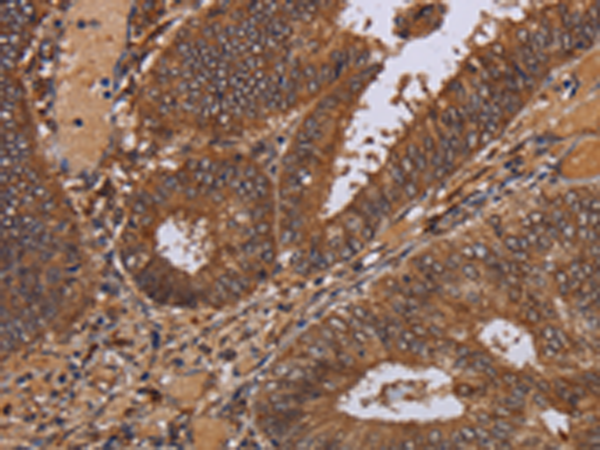

分类: 科研抗体货号: P01531别名: MORG1应用: WB,IHC反应种属: Human, Mouse, Rat

分类: 科研抗体货号: P01583别名: CI-30应用: WB,IHC反应种属: Human, Mouse

分类: 科研抗体货号: P01580别名: B8; CD14; CIB8; MC1DN13应用: WB,IHC反应种属: Human, Mouse

分类: 科研抗体货号: P01606别名: NS; E2IG3; NNP47; C77032应用: WB,IHC反应种属: Human

分类: 科研抗体货号: P01655别名: MPPB; P-52; MPP11; MPPP52; Beta-MPP应用: WB,IHC反应种属: Human, Mouse, Rat

分类: 科研抗体货号: P01604别名: CN1; CNI; CN-I; CN1A; CN-IA应用: IHC反应种属: Human, Mouse